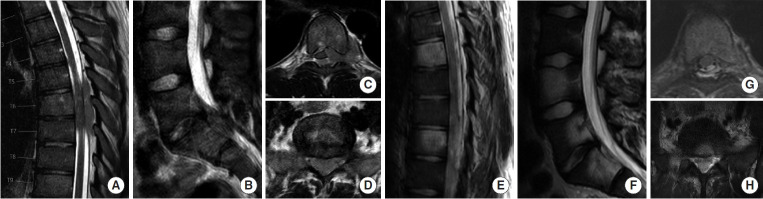

转移性脊柱疾病是一种日益增长的治疗挑战,需要在纳入新兴技术和尊重临床决策基本原则之间取得平衡。辅助治疗的进步,包括立体定向体放疗(SBRT)和化疗,显著提高了患者的长期生存率。手术决策应以完善的框架为指导,如NOMS(神经学、肿瘤学、机械、系统)标准、ESCC(硬膜外脊髓压迫)评分和SINS(脊柱不稳定肿瘤评分),以确保结构化和循证治疗方法。微创技术的整合,包括经皮内固定、消融技术和双门静脉内窥镜入路,降低了手术发病率,促进了更快的恢复。此外,碳纤维植入物通过更好地观察术后任何局部复发和更容易的放射计划,彻底改变了脊柱稳定。SBRT已成为一种关键的方式,提供精确的高剂量辐射,对脊髓的毒性最小,改善局部肿瘤控制和患者预后。多学科方法仍然是最重要的,需要脊柱外科医生、放射肿瘤学家和内科肿瘤学家之间的合作。在这篇叙述性综述中,我们旨在全面概述脊柱转移性肿瘤治疗的现状,重点是:(1)转移性脊柱护理的基础,(2)微创手术技术,(3)碳纤维螺钉的使用,(4)SBRT,(5)最大化患者安全的方法。

Metastatic spine disease represents a growing therapeutic challenge that demands a balance between incorporating emerging technologies while respecting the fundamental principles during clinical decision-making. Advances in adjuvant therapies, including stereotactic body radiotherapy (SBRT) and chemotherapy, have significantly improved long-term patient survival. Surgical decision-making should be guided by well-established frameworks such as the NOMS (neurologic, oncologic, mechanical, systemic) criteria, the ESCC (epidural spinal cord compression) scale, and the SINS (spinal instability neoplastic score), ensuring a structured and evidence-based approach to treatment. The integration of minimally invasive techniques, including percutaneous instrumentation, ablation techniques, and biportal endoscopic approaches, has reduced surgical morbidity and facilitated faster recovery. Additionally, carbon fiber implants are revolutionizing spinal stabilization by allowing better postoperative visualization of any local recurrence and easier radiation planning. SBRT has emerged as a critical modality, offering precise, high-dose radiation with minimal toxicity to the spinal cord, improving local tumor control and patient outcomes. A multidisciplinary approach remains paramount, requiring collaboration between spine surgeons, radiation oncologists, and medical oncologists. In this narrative review, we aim to provide a comprehensive overview of the current state of metastatic spine tumor management, focusing on: (1) fundamentals of metastatic spine care, (2) minimally invasive surgical techniques, (3) the use of carbon fiber screws, (4) SBRT, and (5) ways to maximize patient safety.